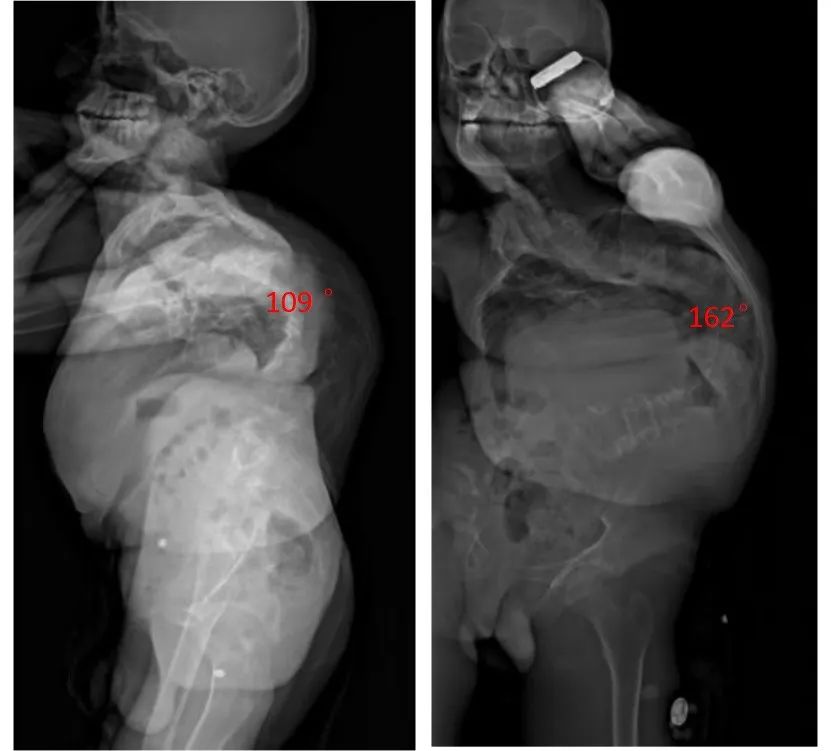

但小寶的病情沒有得到明顯控制。相反,其背部彎曲程度逐漸加重。3年多後,脊柱側彎角度達162度,後凸109度,出現明顯的軀幹失衡、心肺壓迫,嚴重影響生活質量。

小寶術前的影像學結果。圖源/受訪者提供